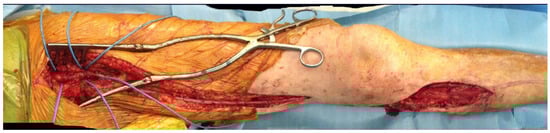

2.2. Technique